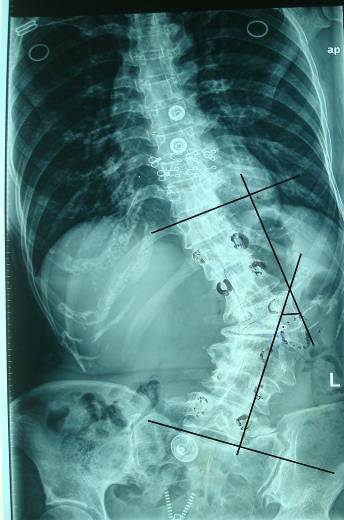

——骨脊柱一区成功开展严重侧弯合并后突畸形患者矫形手术

入住我院的这名患者是属于先天脊柱畸形,有半椎体,有角度侧突,有较大后突,还有椎体旋转,并且是成年人,畸形已经完全僵硬,畸形处还有许多坚硬的增生骨,已形成骨桥连接了上下椎体,就像汉白玉石一样坚硬,因此,术中截骨相当困难。

手术前

手术后